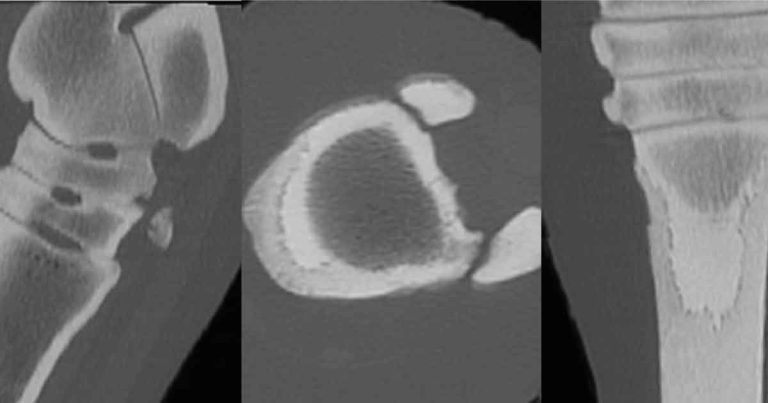

In recent years, a huge increase in more advanced imaging techniques (Figures 4, 5 and 6) has become available and although these techniques are not routinely used, in certain circumstances they can be invaluable in determining the correct treatment strategy and establishing a realistic prognosis for complex cases – preventing treatment that is likely to be unsuccessful. MRI has been widely used to determine which structures are involved in nail penetrations to the solar surface of the foot and is now an established technique to allow accurate treatment of such injuries3.